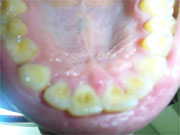

東京都江東区 19歳 男性

あと過蓋咬合も直したいと思ってます。

歯並びは、ご指摘のとおり「過蓋咬合」です。喉の奥を少し調べてみる必要があると思いますが、おそらく保険は効かない普通の矯正治療だと思われます。

けれど、顎関節に影響を及ぼしやすいので一度矯正の専門の医院に相談に行ってみてはいかがでしょうか。